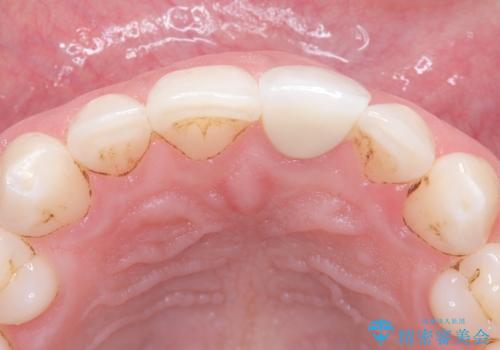

過去に神経の治療をした歯に変色がみられました。ラバーダム防湿の重要性を説明し、予防的に再根管治療から行い、被せ物をすることとなりました。

なるべく隣の歯と調和するようにしました。大変ご満足いただけました。